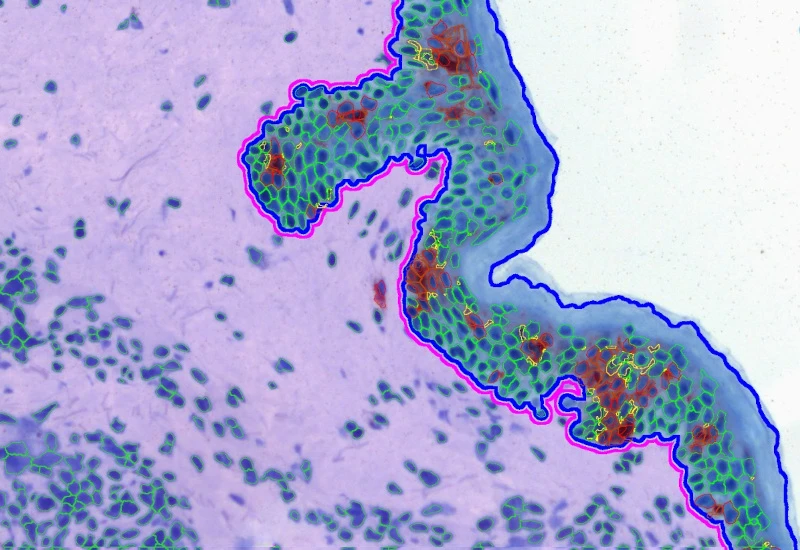

The IF Immune Status in Situ App provides a phenotypic characterization of immune cells in reference to detected metastructures (e.g., tumors, glands) and measures the distance of detected cellular objects to the metastructure boundary (within and/or outside). Distance ranges are also definable. Each segmented cell compartment is measured for up to 20 intensity, statistic, and morphometric parameters, as well as the distance of each cell to the areas boundary.

The IHC Tumor-Stroma App combines the segmentation of tumor and stroma (based on the morphology) and the detection of specifically stained cell populations. It segments the cells into their nucleus, perinuclear area, and/or cytoplasm. Each segmented cell compartment in tumor and/or stroma is measured for up to 20 intensity, statistic, and morphometric parameters that can be displayed in and exported into scattergrams and histograms.

The Tumor Foci App allows for the detection of the whole tissue and, more importantly, tumor foci based on nuclear structure analysis, mainly on HE staining. The number, area, and density of tumor foci are measured.

The IF Cellular Microenvironment App allows to determine the cellular phenotype of specific IF-stained cell populations and establishes their spatial relationship between each other and their neighboring cells/cell populations, including those with metastructures (e.g., blood vessels, tumors) in their vicinity. It is especially suited for proximity and infiltration analyses.

The IF Tumor Vascularization App provides tissue detection, including the separation of tumor tissue and tumor stroma (healthy tissue). Additionally, it detects blood vessels based on appropriate stains (e.g., CD31) and measures the number, area, and density of these blood vessels. The vessel detection also can be set to close open stained vessel walls and to connect separated vessel sections within a definable distance.

The IHC Tumor-Macrophages App provides tissue detection, including the separation of tumor and healthy tissue. It detects macrophages based on specific staining (e.g., CD68) and outputs the area of macrophages within tumor and healthy tissue.

Image: Courtesy of Dr. Patrick Michl, Dr. Maren Egidi, and Dr. Heidi Griesmann, Universitätsklinikum Halle (Saale).

The IHC Tumor Vascularization App provides tissue detection, including the separation of tumor tissue and tumor stroma (healthy tissue). Additionally, it detects blood vessels based on appropriate stains (e.g., CD31) and measures the number and area of these blood vessels. The vessel detection can also be programmed to close open stained vessel walls and to connect separated vessel sections within a definable distance. The App outputs the number, density, and areas of vessels within both tumor and healthy tissue.